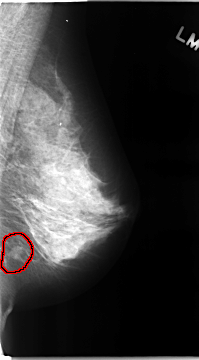

C_0104_1.LEFT_MLO

FILE: C_0104_1.LEFT_MLO.OVERLAY

TOTAL_ABNORMALITIES 1

ABNORMALITY 1

LESION_TYPE MASS SHAPE IRREGULAR MARGINS MICROLOBULATED

ASSESSMENT 5

SUBTLETY 5

PATHOLOGY MALIGNANT

TOTAL_OUTLINES 1

BOUNDARY